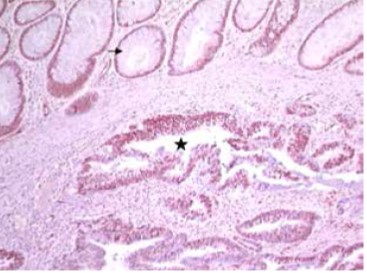

Figure 2 : TNE bien différenciée grade2

Figure 3 :carcinome neuro-endocrine